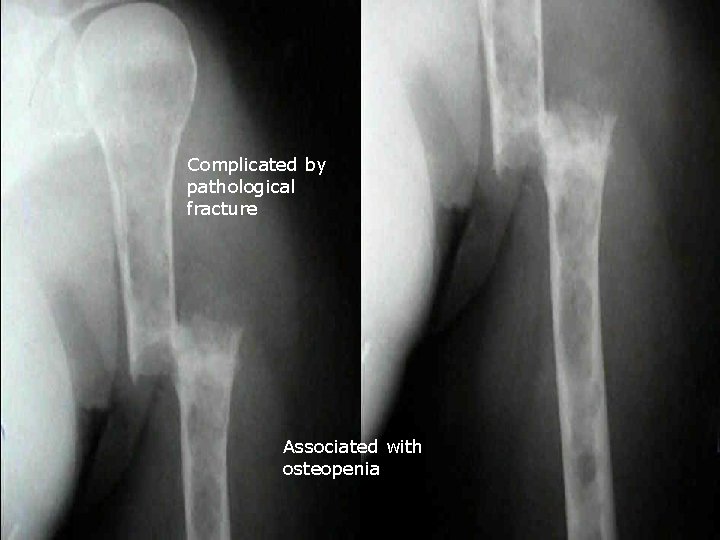

Mulyiple osteolytic Punched-out lesion

Mulyiple osteolytic Punched-out lesion Absence of perilesional sclerosis

Complicated by pathological fracture Associated with osteopenia

PET PET-CT coronal view

Regarding Multiple Myeloma : a. It is the commonest 1 ry neoplasm of bone (√ ) b. Generalised osteopenia is a recognised appearance (√ ) in 15 % c. Scintigraphy over-estimates disaese d. (X ) under estimates Lesions becomes scleotic following extent chemotherapy e. ) also following Vertebral pedicle(√ destruction is an radiotherapy early event (X ) (Ref: Grainger and Allison pp 1913 -1915, Daenhartppp 121 -122, Chapman 2003 pp 575 -576)